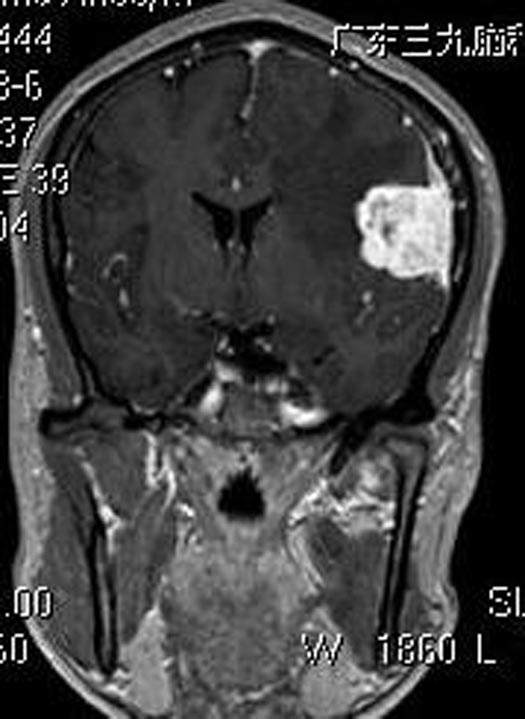

万万没有想抽搐竟是脑袋里长了肿瘤!一家人赶紧来到广东三九脑科医院。头颅MR检查显示:左侧额颞部颅骨内板下示不规则宽基底占位病灶,病灶范围约26.1mm×38.9mm×30.2mm。

综合神经外科鲁明主任主刀,在全麻下行左侧额颞部脑膜瘤切除术,显微镜下见肿瘤呈灰白色,鱼肉状,质中,边界较清,血供丰富,镜下将肿瘤顺利全切。术后病理结果提示:过渡型脑膜瘤,WHO I级。

▲术前MR